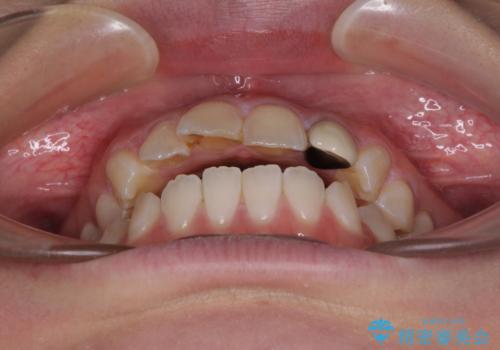

途中1年8ヶ月ほど来院されず、久しぶりの来院後は治療が面倒とのことで、前歯の叢生や隙間に不十分な点が残った状態での終了となりました。